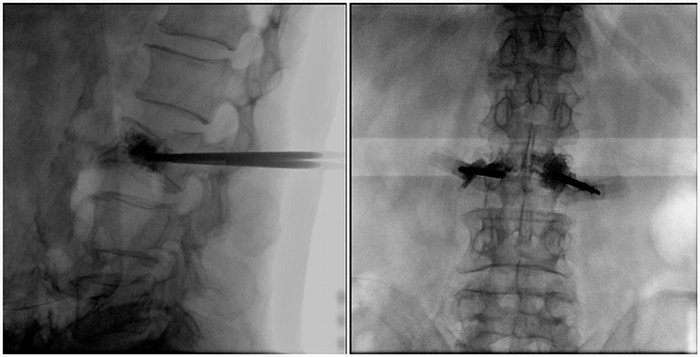

術(shù)中切口5毫米,在大平板C臂機的透視指引下,確定了進針的方向及進針的深度。經(jīng)椎弓根向椎體置管,建立通道,插入骨擴張器(球囊)。球囊擴張恢復(fù)椎體高度,并在椎體內(nèi)形成空腔,確定骨水泥的注入劑量,并注入骨水泥觀察其擴散情況。

大平板C臂機臨床圖像